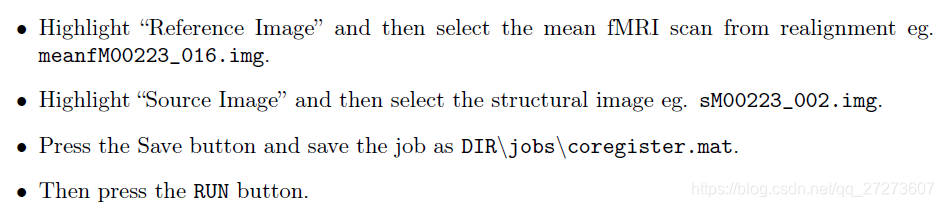

2.2 Coregistration配准

在fmr初始界面选择Coregister,然后按照如下指令操作。

SPM将在结构像数据和功能像数据建立起关联,